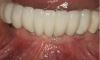

The patient shown in Figure 1 had presented after significant endodontic-related abscesses reduced the height of both buccal and lingual plates of bone. Covering the biphasic calcium sulfate (BPCS) graft with a dense polytetraflouroethylene (PTFE) barrier for 3 weeks enhanced healing in the site. Clinically, it is apparent that the ridge volume was maintained over 5 years and supported keratinized tissue (Figure 2). Most importantly, there was, on histologic evaluation, 58% vital bone, with no remnants of the bone replacement graft material (Figure 3).

Fig 3. Although the graft had only been in situ for 4 months, the resulting histology demonstrated 58% vital bone, no remnants of graft material, and a dense trabecular nature. (Histology sample provided by Dr. Rohrer and Mr. Prasad.)

Figure 3